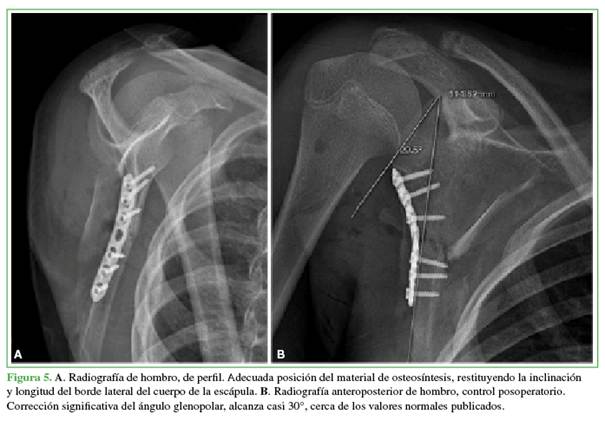

Se liberaron los fragmentos debido al abundante callo óseo con signos de consolidación a fin de mejorar la movilidad del fragmento en el foco de fractura y así recuperar la longitud de borde lateral de la escápula. La reducción se efectuó con pinzas reductoras y fijación provisional con clavos de Kirschner para alinear los fragmentos superior e inferior, y, en conjunto, lograr corregir el ángulo de la pared lateral, fijándola con la placa premoldeada en la región proximal y con tornillos corticales en el borde lateral (Figura 4).

La alineación, la reducción y la ubicación del material de osteosíntesis se confirmaron con el intensificador de imágenes. Se logró una adecuada angulación de cada tornillo sin disposición intrarticular. Se cerró la herida por planos y se evaluó de inmediato la movilidad del hombro. Los arcos de movilidad pasiva y activa asistida habían mejorado considerablemente. La paciente continuó usando un cabestrillo hasta el control posoperatorio.

En las radiografías posoperatorias, se observó una alineación satisfactoria, con una reducción anatómica y posicionamiento del material de osteosíntesis. El cuerpo escapular fue reparado en su borde lateral, esto mejoró la estabilidad en el foco de fractura con la posición de la placa premoldeada. Se observó una mejor alineación gleno-humeral, logrando una restitución y un aumento del ángulo glenopolar, la corrección de la inclinación del segmento distal del foco de fractura y la alineación del cuerpo respecto a la radiografía lateral preoperatoria (Figura 5).